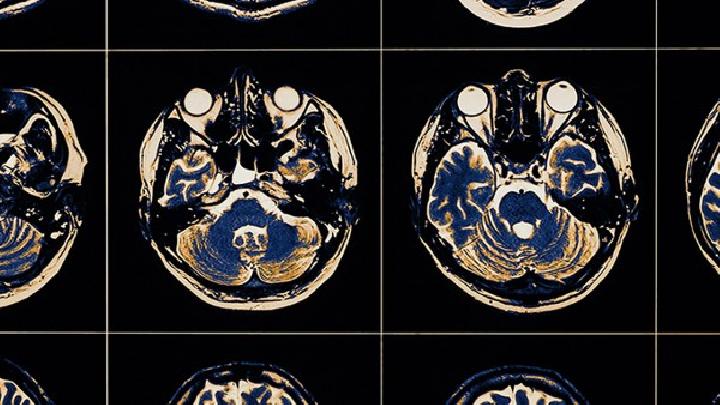

痉挛性脑瘫主要表现为肌张力增高、运动障碍、姿势异常及反射异常等症状,病情严重程度从轻度运动受限到完全丧失自主活动...

一个月大的脑瘫患儿可能出现肌张力异常、喂养困难、原始反射消失延迟、姿势异常等症状表现。 1、肌张力异常 患儿可能...

脑瘫可能由产前缺氧、早产低体重、新生儿黄疸、遗传代谢异常等原因引起,症状表现为运动障碍、肌张力异常等,需通过康复...

脑瘫的临床表现主要有运动发育迟缓、肌张力异常、姿势异常、伴随症状等,需根据具体类型综合评估。 1. 运动发育迟缓...

小儿脑瘫的症状表现主要包括运动发育迟缓、肌张力异常、姿势反射异常、语言障碍等,严重者可伴随智力障碍或癫痫发作。 ...

新生儿脑瘫的早期症状主要表现为肌张力异常、运动发育迟缓、姿势反射异常以及喂养困难。 1、肌张力异常 患儿可能出现...